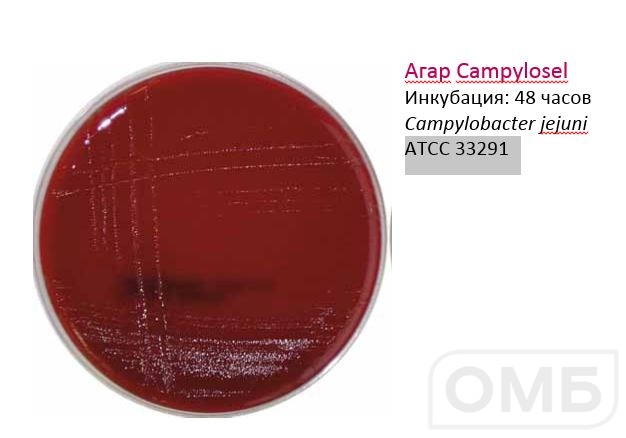

Кампилобактер фетус: патогенез и инфекции

/evrimagaci.org%2Fpublic%2Fcontent_media%2Fb099374a4578fc241a0555a594831216.jpeg)